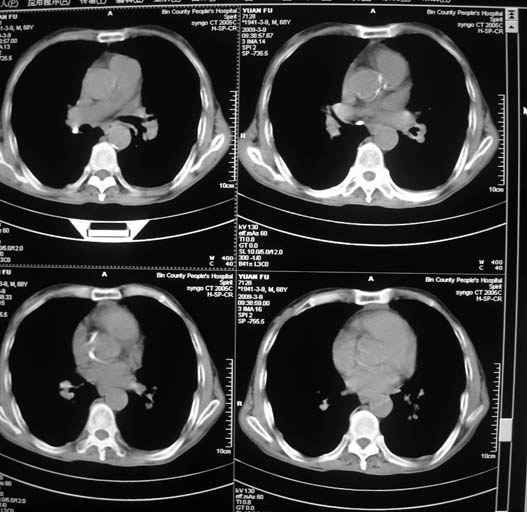

男,68岁,左上肺占位,肺门淋巴结转移?

1)考虑左肺上叶尖段周围型肺癌并阻塞性肺炎,纵隔淋巴结转移。2)心包少量积液。

1)考虑左肺上叶尖段周围型肺癌并阻塞性肺炎,纵隔淋巴结转移。2)心包少量积液

1)考虑左肺上叶尖段周围型肺癌并阻塞性肺炎,纵隔淋巴结转移。

2)心包少量积液。